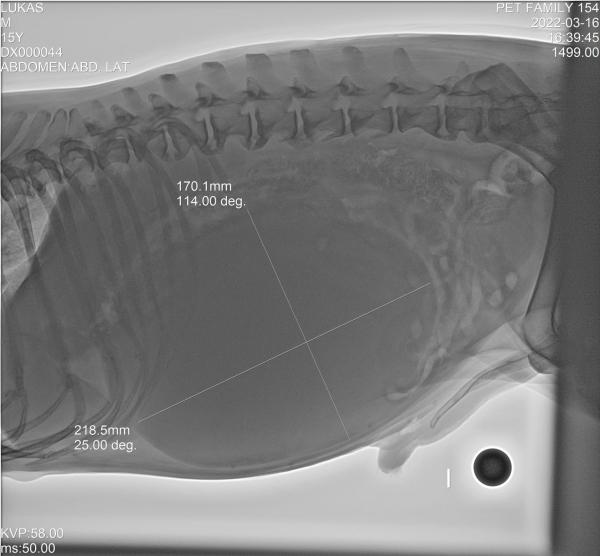

Tengo un perrito criollo que tiene 15 años. Es un perrito muy vital para su edad. Hace dos meses empezó una inflamación en el estómago y hasta ahora lo lleve al veterinario. Me indica el veterinario que tiene anemia ya que salió el examen en 3.800 y que debe ser más alto. También me dice que tiene el vaso muy inflamado (actualmente mide 17 * 21 CMS) y que debe quitárselo. Adjunto imágenes de las radiografías practicadas pero no sé qué hacer si operarlo o no. Me preocupa mucho, más cuando caso quedaría sin sistema inmune. Agradecería un consejo al respecto.

María Besteiros

Hola, la decisión de extirpar o no el bazo la tiene que tomar el veterinario, valorando las ventajas y los inconvenientes. El perro no se queda sin sistema inmune sin el bazo, este es solo una de las partes de este sistema. Hay muchos perros que viven sin él, de hecho, yo tengo una perra de 12 años y medio que lleva año y medio sin bazo, y no tienen ningún problema. En cualquier caso, es el veterinario quien tiene que justificar su decisión. Un saludo.